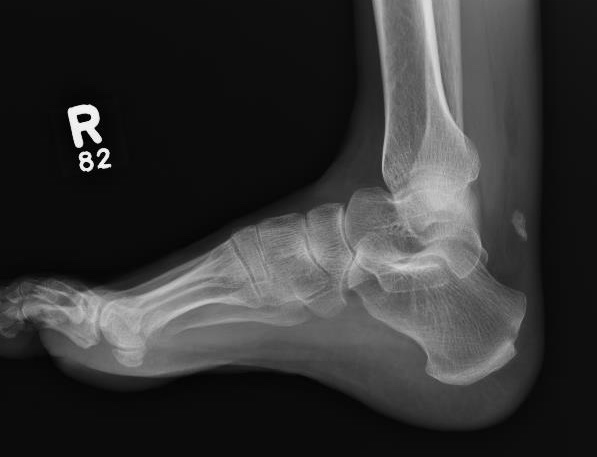

Xray

Exclude bony avulsion / insertional rupture